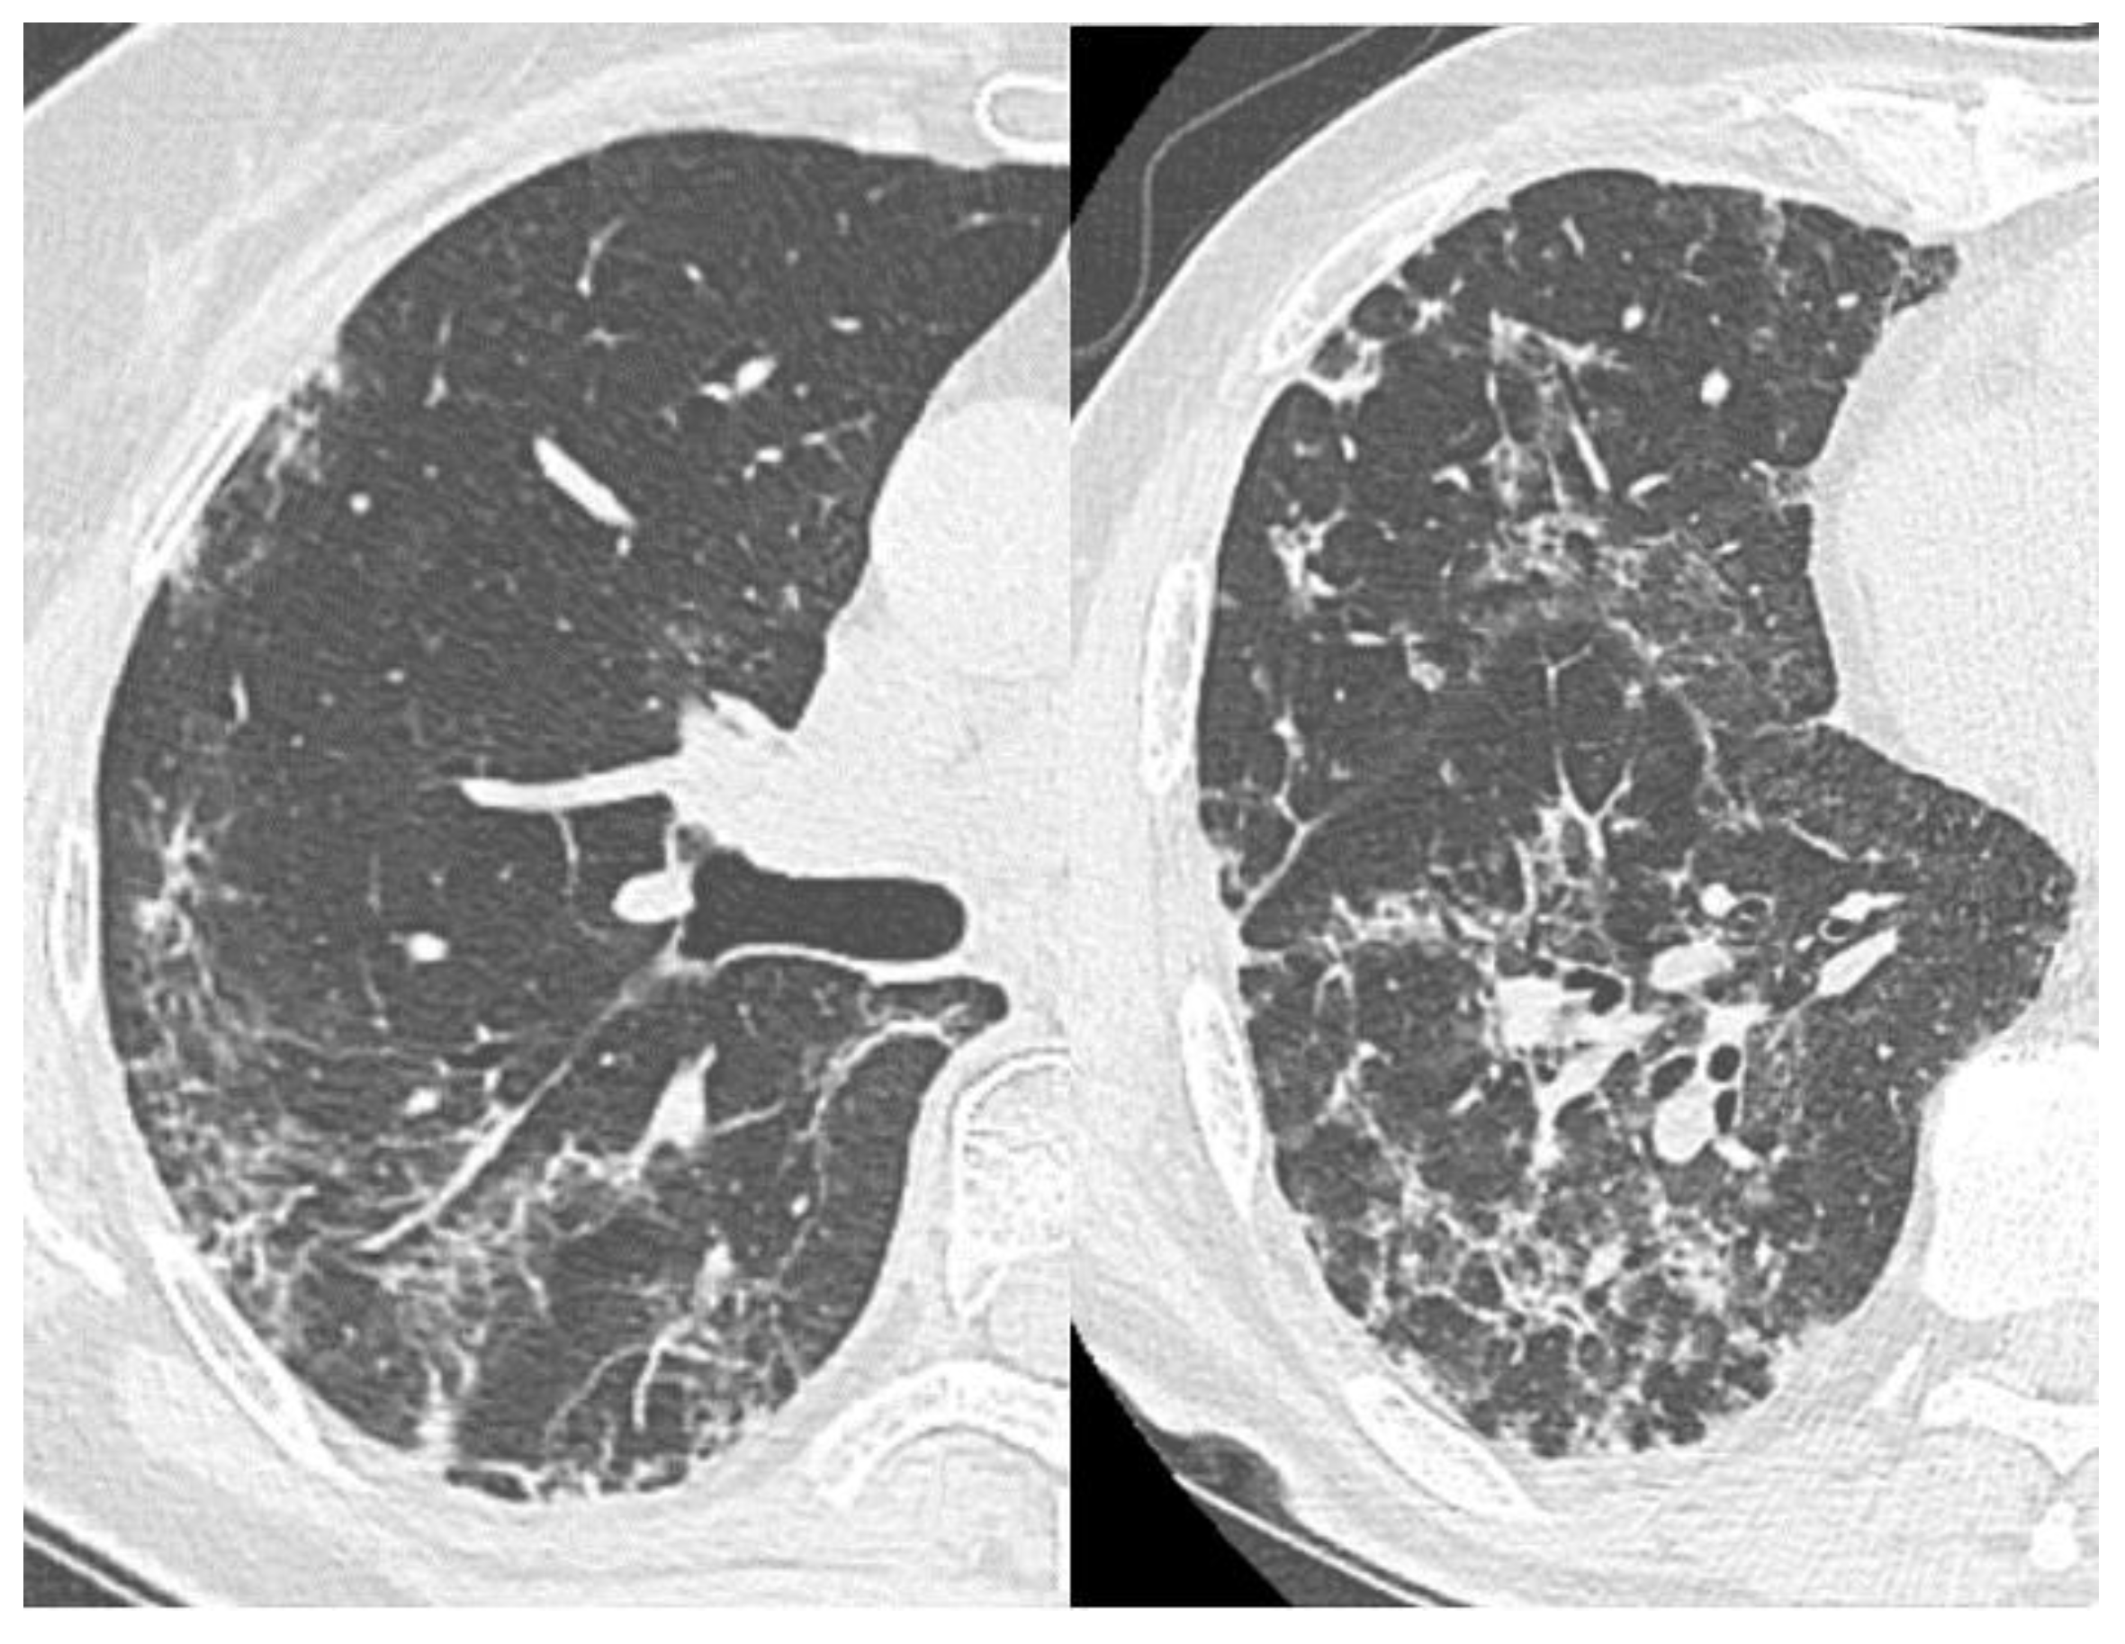

3.3. Dynamics of CT Changes over Time

- Early or initial (0–4 days): GGO type changes dominated in both cohorts, but almost 67% of deceased CT studies had CP pattern in this phase of disease, almost half of studies demonstrated mixed GGO-consolidation changes;

- Progressive (5–8 days): an increase in the volume of the GGO, appearance and increase CP (56% of recovered patient’s studies, 73%—deceased), consolidations (57% of recovered patient’s studies, 87%—deceased) type lesions in both cohorts, RC presented in half of the studies;